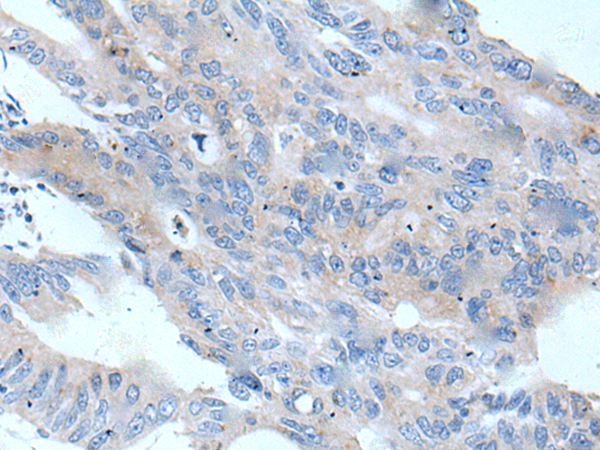

分类: 科研抗体货号: P12906别名: VT; VT4应用: IHC反应种属: Human, Mouse